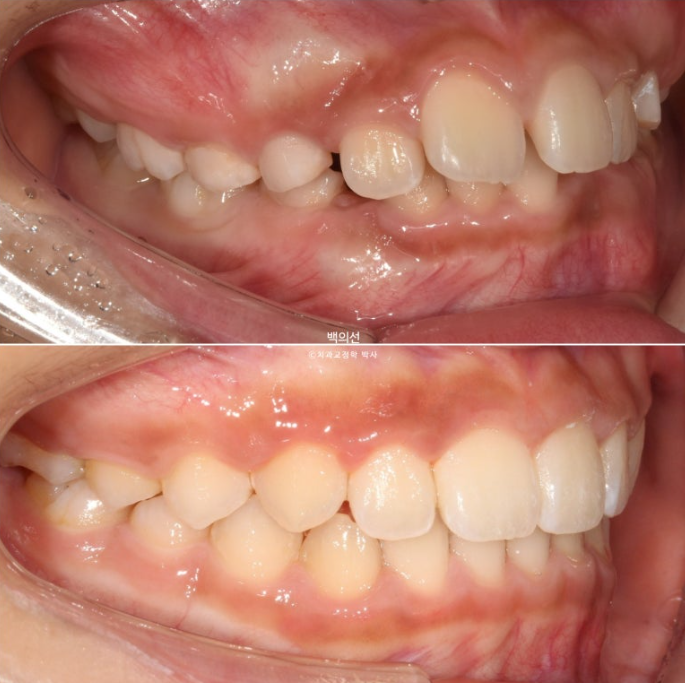

23.07

교정치료를 위해 온 만 9세 어린이입니다.

부모님이 고치고 싶은 것은 앞니가 깊게 물리는 과개교합

아래 앞니가 보이지 않을 정도의 심한 과개교합입니다.

앞니 돌출이 있으며

악궁전반부가 좁습니다.

아래도 마찬가지로 악궁확장이 필요합니다.

이 날 공간이 부족하여 앞니가 삐뚤게 나왔고 곧 나올 송곳니는 공간이 부족하여 덧니로 나올 상황입니다.

인비절라인 퍼스트를 권유드렸고 23년 8월부터 장치를 끼기 시작했습니다.

물샐틈 없는 1급 교합관계를 보입니다.

교합의 개선